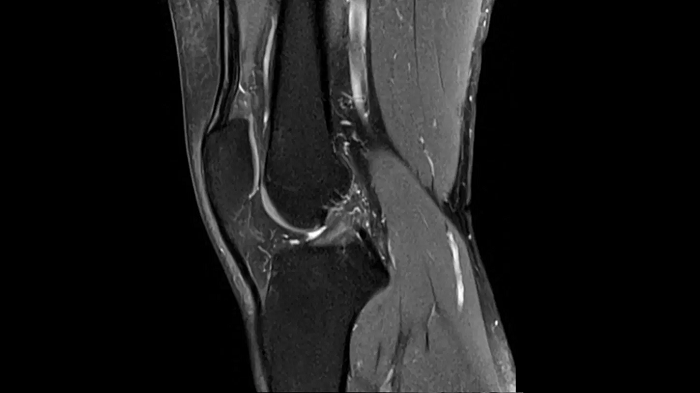

3D MSK Imaging with Compressed Sensing

Knee imaging with T2w SPACE can be expedited using Compressed Sensing to reduce acquisition times, offering high-resolution images for uncompromised knee assessments.

Compressed Sensing 6

0.3 x 0.3 x 0.6 mm2

TA 4:15 minutes

MAC-ID: 7aaaa0175.

MAC-ID: 7aaaa0175. Image Credit: Siemens Healthineers